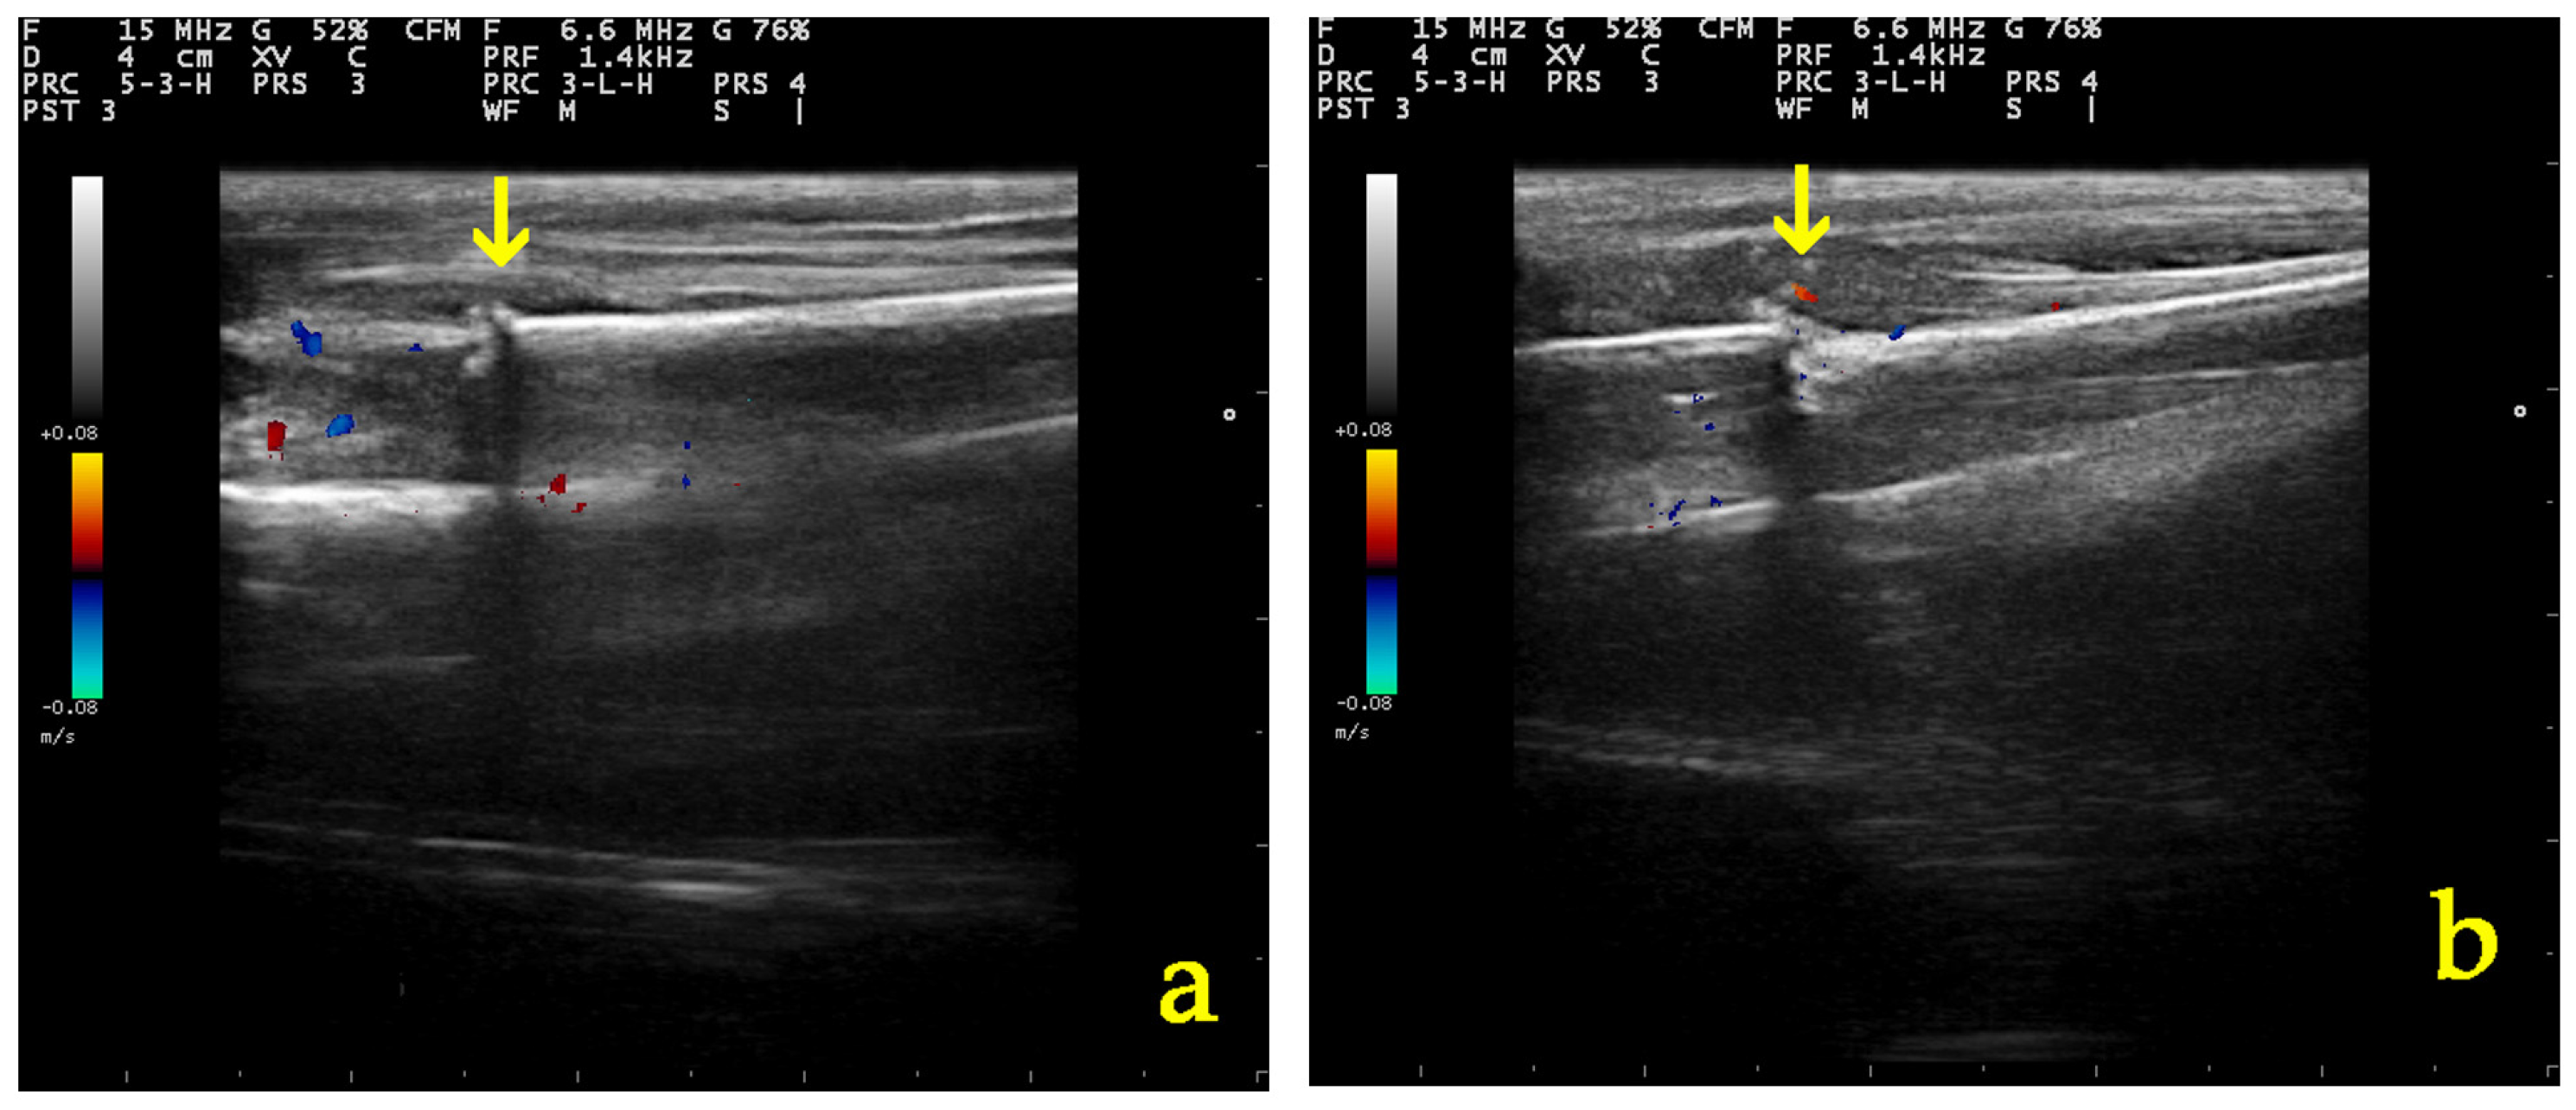

3.5.1. Ultrasonographic Examination

3.5.2. Radiographic Examination

- Caruso, G.; Lagalla, R.; Derchi, L.; Iovane, A.; Sanfilippo, A. Monitoring of Fracture Calluses with Color Doppler Sonography. J. Clin. Ultrasound 2000, 28, 20–27. [Google Scholar] [CrossRef]

| Parameter of Ultrasonographic Examination | Group | D0 | D5 | D10 | D20 | D28 |

|---|---|---|---|---|---|---|

| Echogenicity and structural organization of the tissue at the fracture site | A | 1 (1–1) | 2 (1–2) | 2 (2–2) | 3 (3–4) | 3.5 (3–4) |

| B | 1 (1–1) | 1 (1–2) | 2 (2–2) | 3 (2–4) | 4 (2–4) | |

| Formation of the callus and the vascularization present at the osteotomy | A | 1 (1–1) | 2 (2–2) | 2 (2–2) | 3 (2–4) | 3.5 (3–4) |

| B | 1 (1–1) | 2 (2–2) | 2 (1–2) | 3 (2–4) | 4 (2–4) | |

| Total grade | A | 1 (1–1) | 1.5 (1–2) | 2 (2–2) | 3 (3–4) | 3.5 (3–4) |

| B | 1 (1–1) | 1 (1–2) | 2 (2–2) | 3 (2–4) | 4 (2–4) |